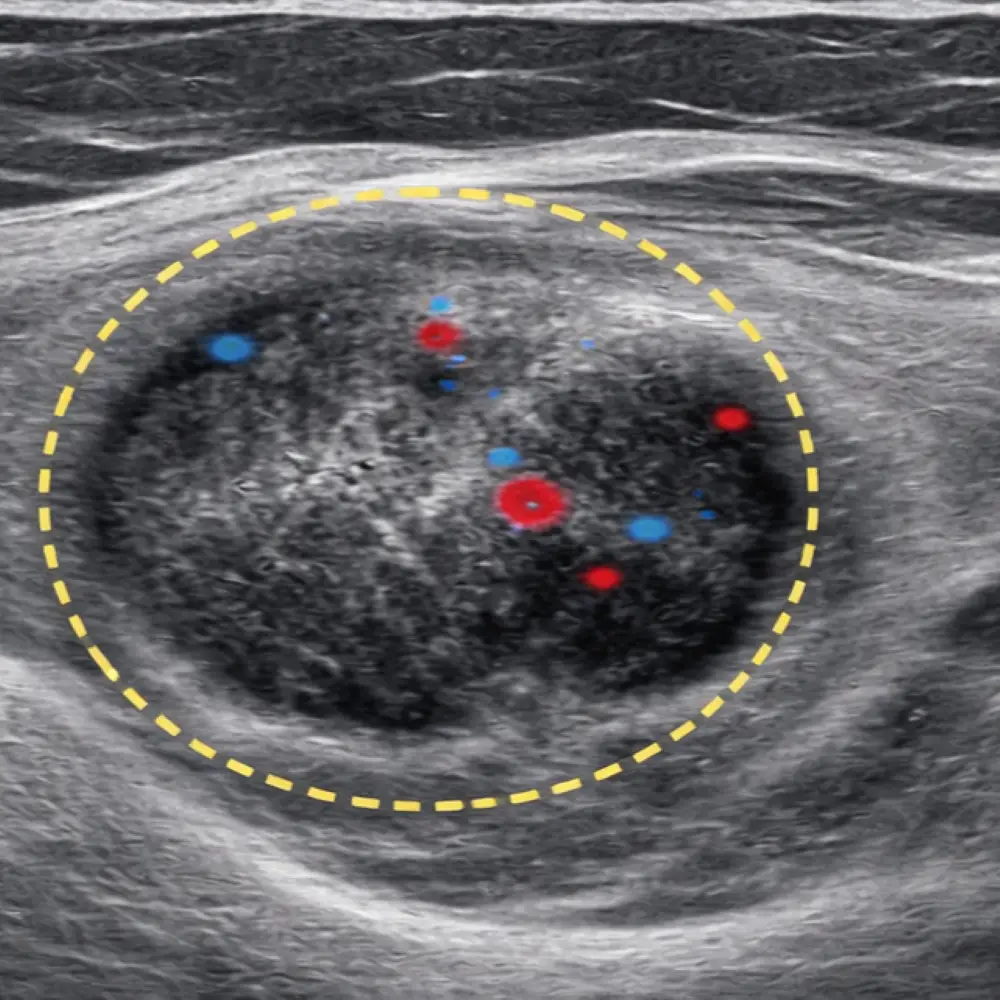

Fibroadenoma